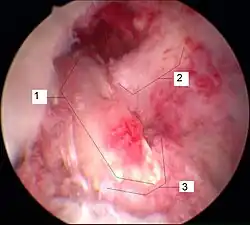

Sonderfall knöcherner Ausriss

Der knöcherne Ab- oder Ausriss des vorderen Kreuzbands vom Knochen (Schienbein oder Femur) ist wesentlich seltener als seine intraligamentäre Ruptur[255] und ist definitionsgemäß kein Kreuzbandriss. Dieser Sonderfall tritt häufiger bei Kindern, vor allem im Bereich des Kreuzbandansatzes am Schienbein Eminentia intercondylica auf und hat durch Refixierung des Ausrisses – beispielsweise mit Schrauben oder Drahtnaht – allgemein gute Chancen, wieder vollständig knöchern einzuheilen. Bei der arthroskopischen Refixation der das Kreuzband tragenden Knorpel-Knochen-Schuppe ist eine gute Übersicht von entscheidender Bedeutung, um die Einklemmung des Ligamentum transversum genus (zwischen den Menisken) unter dem Fragment zu vermeiden. Ansonsten ist die Mini-open-Technik vorzuziehen. Generell ist darauf zu achten, mit den Implantaten (Schrauben oder Drahtnähten) die Wachstumsfuge nicht zu blockieren.